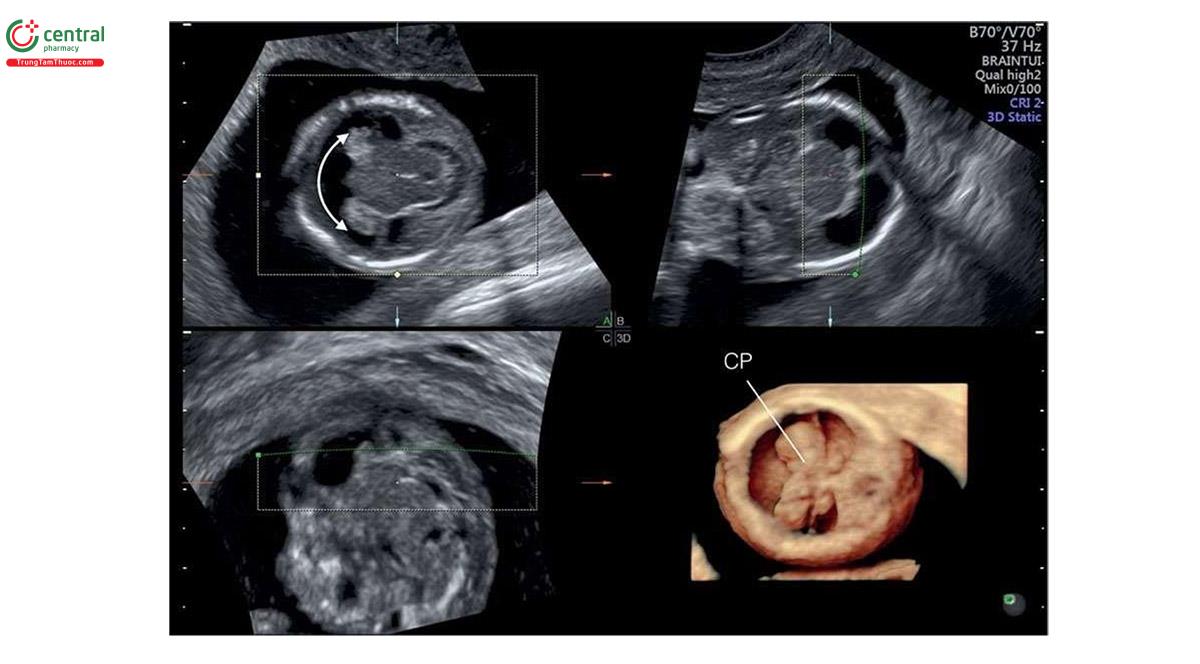

Узи первого триместра форум

Узи первого триместра форум 117 фото